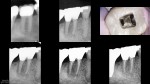

I had a historical on this from 2005…subsequent to which a Zirc was placed.

I took a look at it and knew there wasn't going to be any point in a traditional access…i.e. even if I cut a traditional access, it would be a search and try-not-to-destroy in the roots.  Found four PONs. CBCT in CH to check (not shown).

So instead, I cut a wide swath through the Zirc (stepped access) and accessed each root individually…aka "dual" or "truss" access.

Pure SSW 17/V.04 shapes in all four PONs.

Amalgam crown repair.

About a 7 month followup from today.